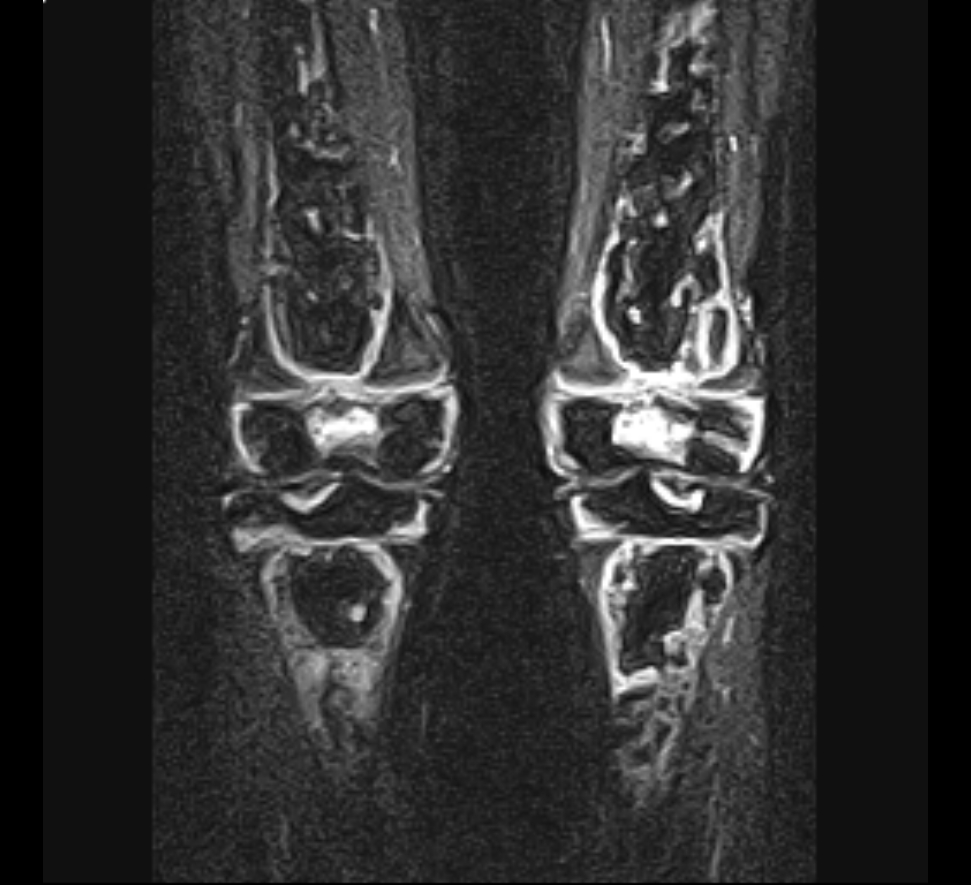

무릎연골 연화증 진단은 슬개골의 정렬 상태를 측정하거나,

무릎 관절 방사선 검사, 보행검사, 초음파 등 다양한 방법을 통해서도 가능하다.